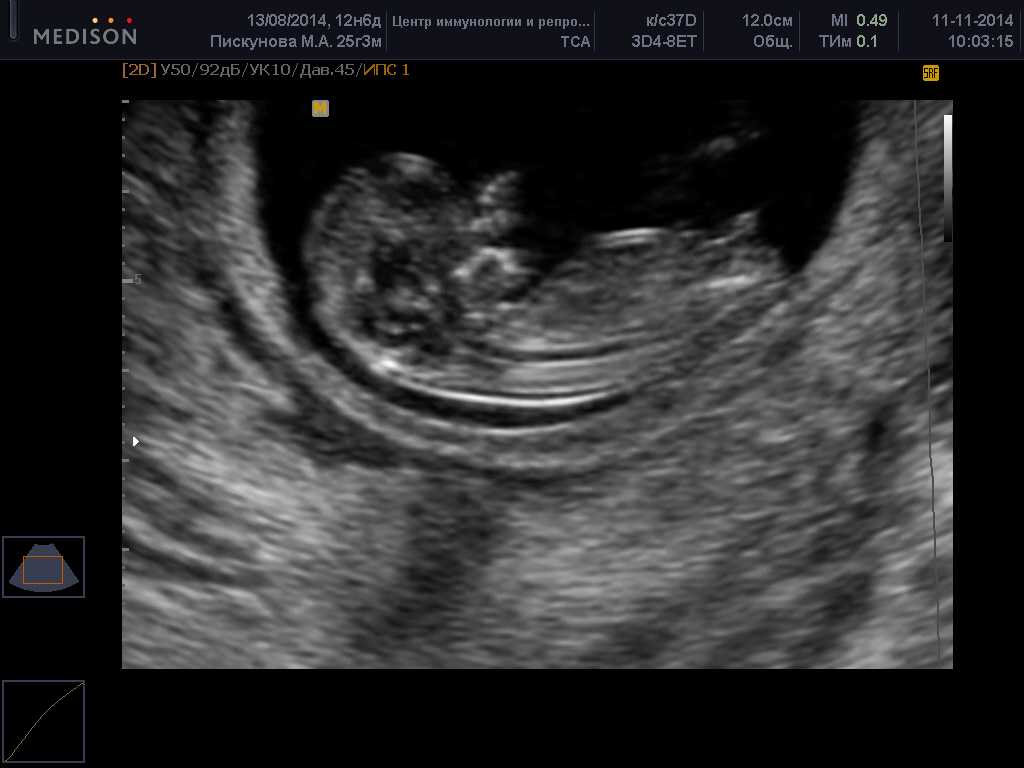

Обычно скрининговое узи 1 триместра не превышает 30 минут. Если исследование проводится трансвагинально, на датчик надевается одноразовый презерватив, затем он вводится во влагалище. При правильном выполнении беременная женщина не должна испытывать дискомфорт.

УЗИ плода 1 триместр фото:

При трансабдоминальном УЗИ передняя стенка живота будущей матери смазывается специальным гелем. Датчик прибора будет скользить по нему, изображение показывается на мониторе. Такое исследование также не вызывает неприятных ощущений у беременной.